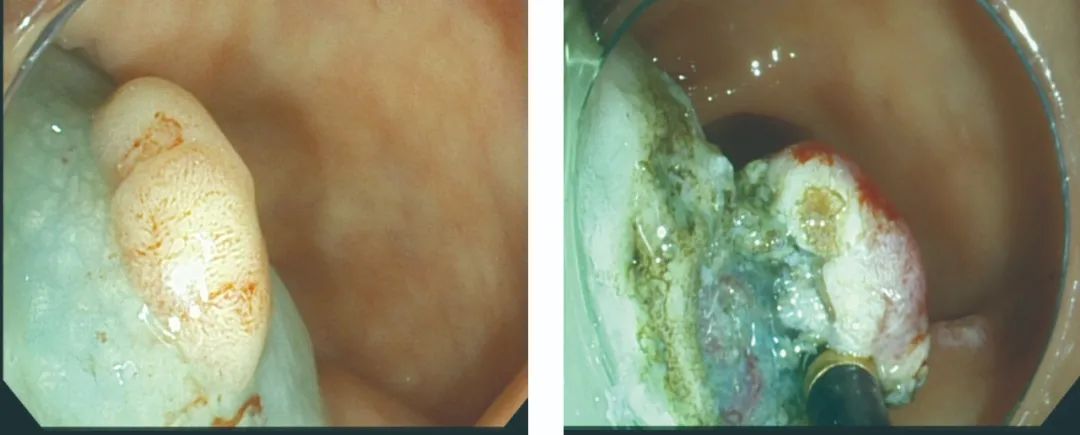

患者选择在我院行ESD早癌剥离术

▲ 黏膜下注射,剥离病灶